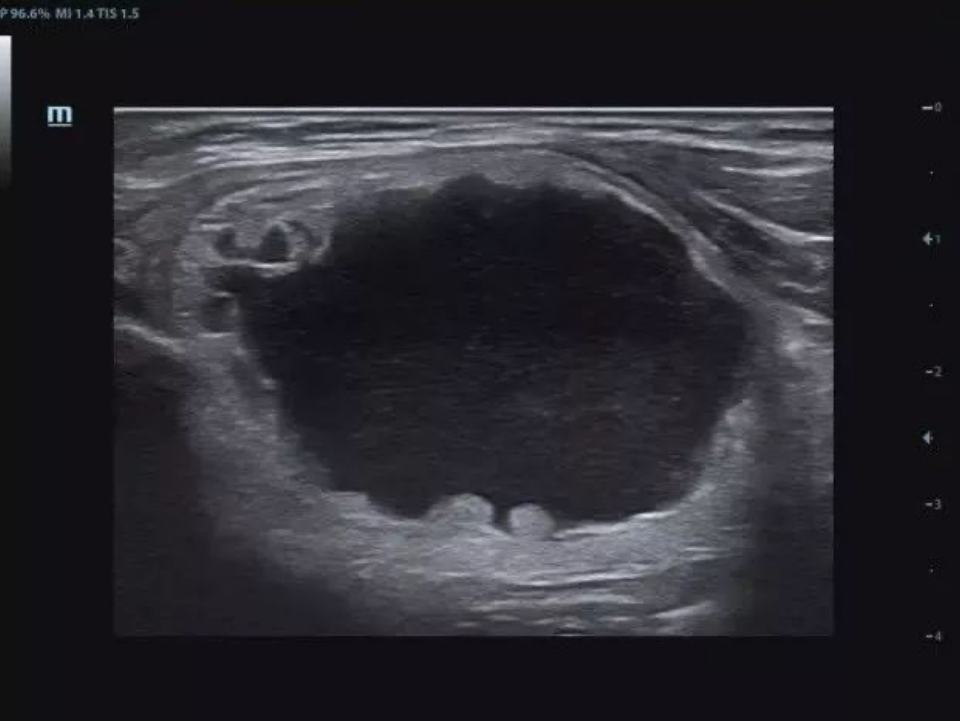

Gallbladder polyp

Single crystal transducers with 3T technology

Mindray's unique single crystal transducers with 3T technology

(Triple-matching layers, Total-cut design and Thermal control) provide a wider bandwidth to simultaneously offer better penetration and higher resolution. Integrating the brand-new single crystal volume, convex and phased array transducers with the system, X-Insight makes an optimum scanning solution in OB/GYN, ABD, Cardiology, and more.